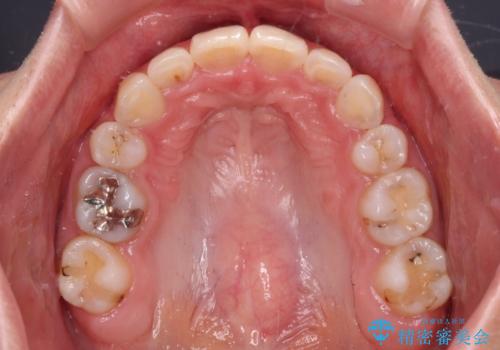

デコボコで飛び出した前歯 ワイヤー装置による抜歯矯正

矯正治療前の咬み合わせで、前歯がすり減ってしまい、歯列が整ったときに先端がガタガタになってしまったため、矯正治療後に形態修正を行いました。